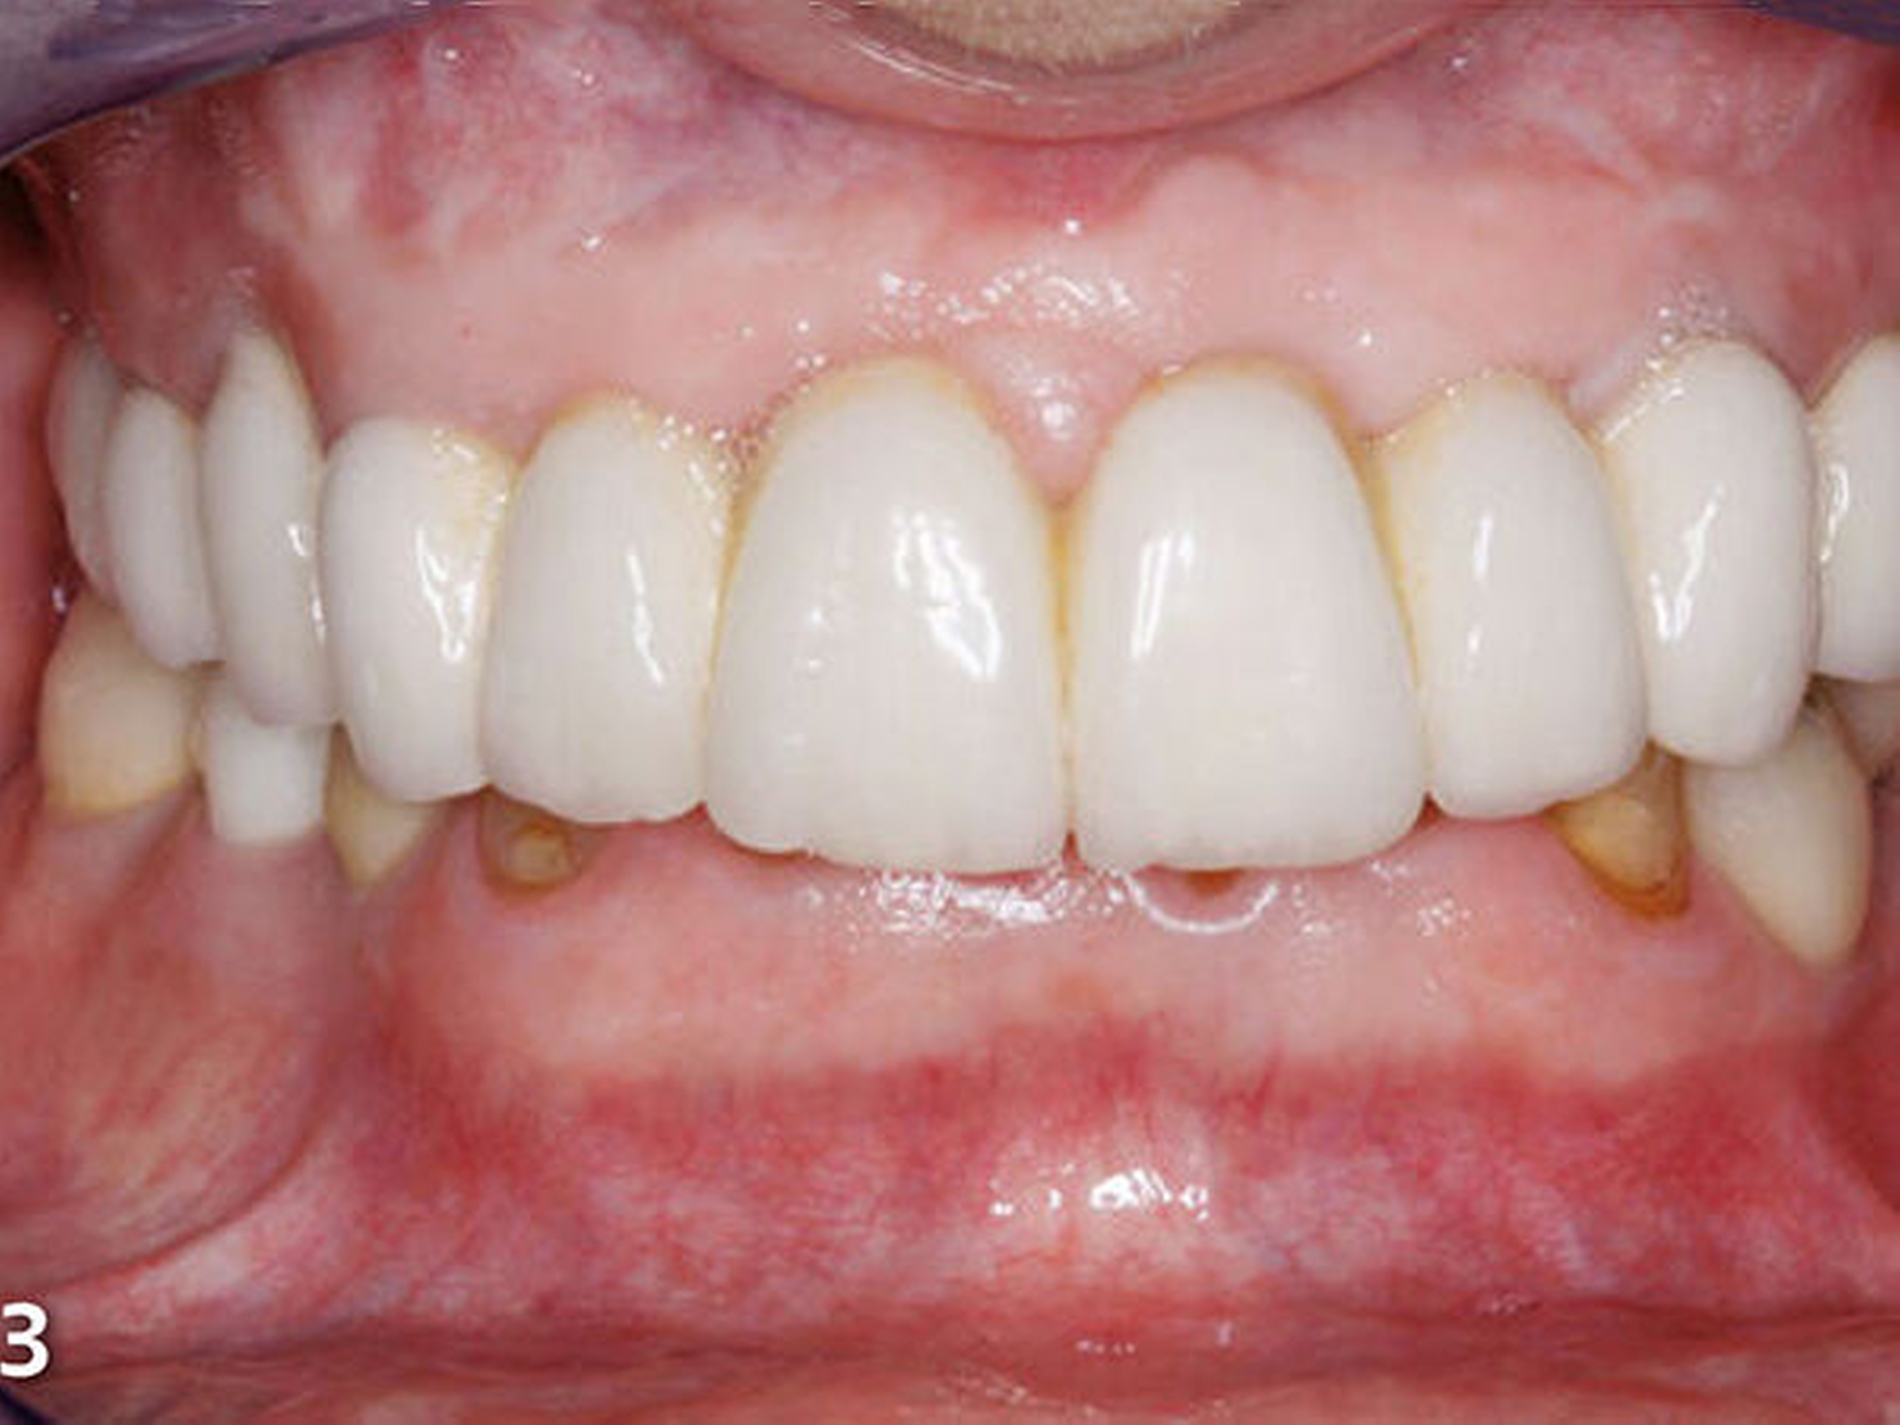

Die Patientin wies deutliche Zeichen von Attrition und Abrasion an den Unterkieferfrontzähnen (Abb.2) und ein Defizit in der vertikalen Distanz der Okklusion auf (Abb.3). Im Unterkieferfrontzahnsegment war eine kompensatorische Eruption des Kieferkamms in Richtung Okklusionsebene eingetreten, die verbreiterte keratinisierte Gingiva gibt darauf einen deutlichen Hinweis (Abb.4) (Bartlett & Smith 2000; Berry & Poole 1976; Cekic Nagas &Ergun2015; Manfredini & Poggio 2016).